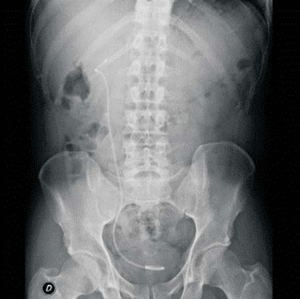

Paciente de sexo masculino de 42 años, fumador intenso, sin antecedentes personales. En enero de 2019, consultó por cólico nefrítico, en esa oportunidad le diagnosticaron discreta ureterohidronefrosis y urolitiasis derecha radiopaca de 8 milímetros. La litiasis migró al cáliz inferior del riñón derecho durante colocación de catéter doble J, el 18 de enero de 2019 (figura 1). Recibió tratamiento con LOEC, la primera sesión resultó inefectiva y se suspendió el procedimiento a los 1.253 disparos a 1,5 de energía dada la imposibilidad de focalización del cálculo por tratarse de un riñón muy móvil. Posteriormente se coordinó un segundo procedimiento, que se realizó el 21 de marzo de 2019, durante el cual se administraron 3.500 disparos a 4 de energía. No se registraron incidentes ni eventos adversos durante el procedimiento, el paciente fue dado de alta a domicilio asintomático.